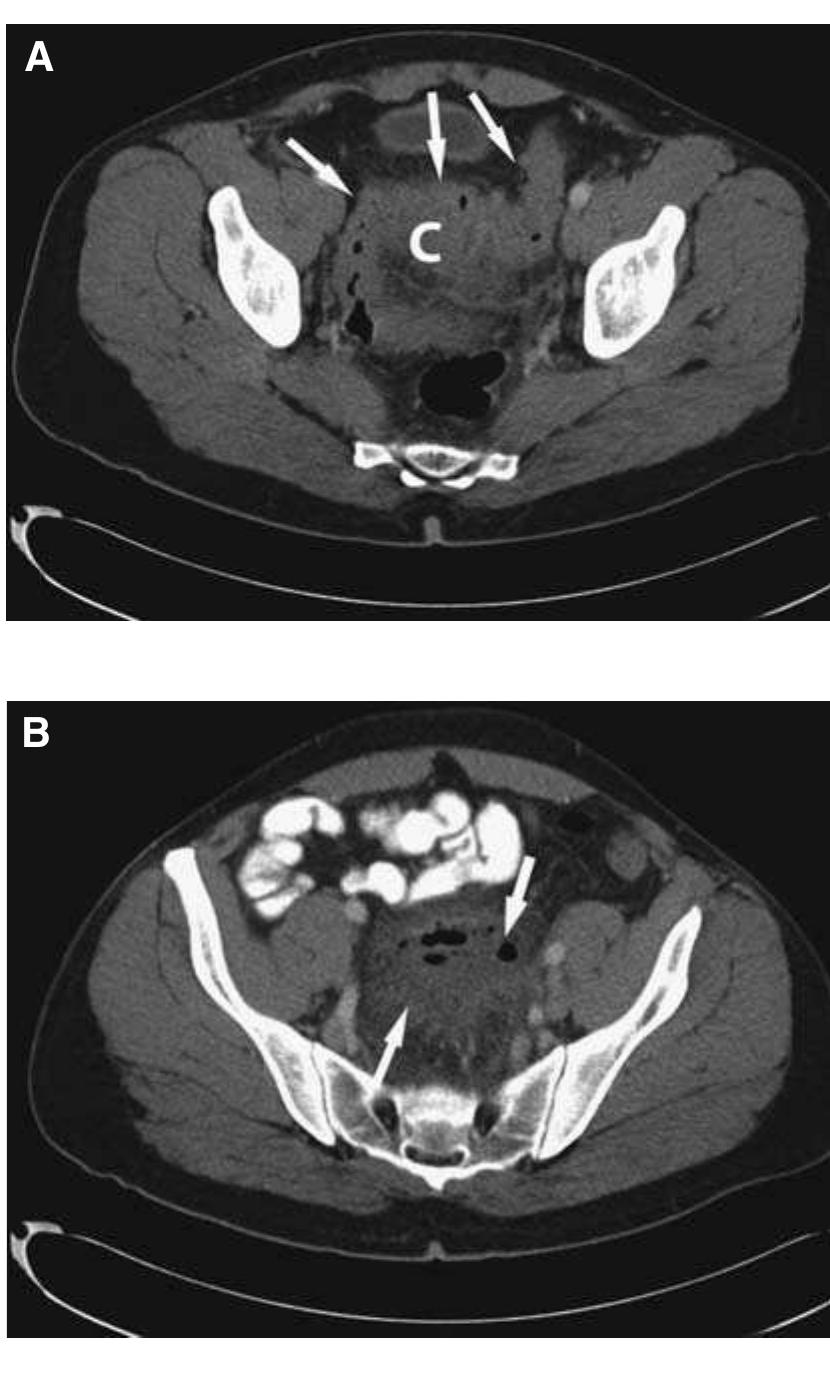

The knee is an anatomically and biomechanically complex joint. Few studies have been published reporting the type and frequency of knee injuries. However, this information that may help to prevent, diagnose, and treat knee joint injuries.... more